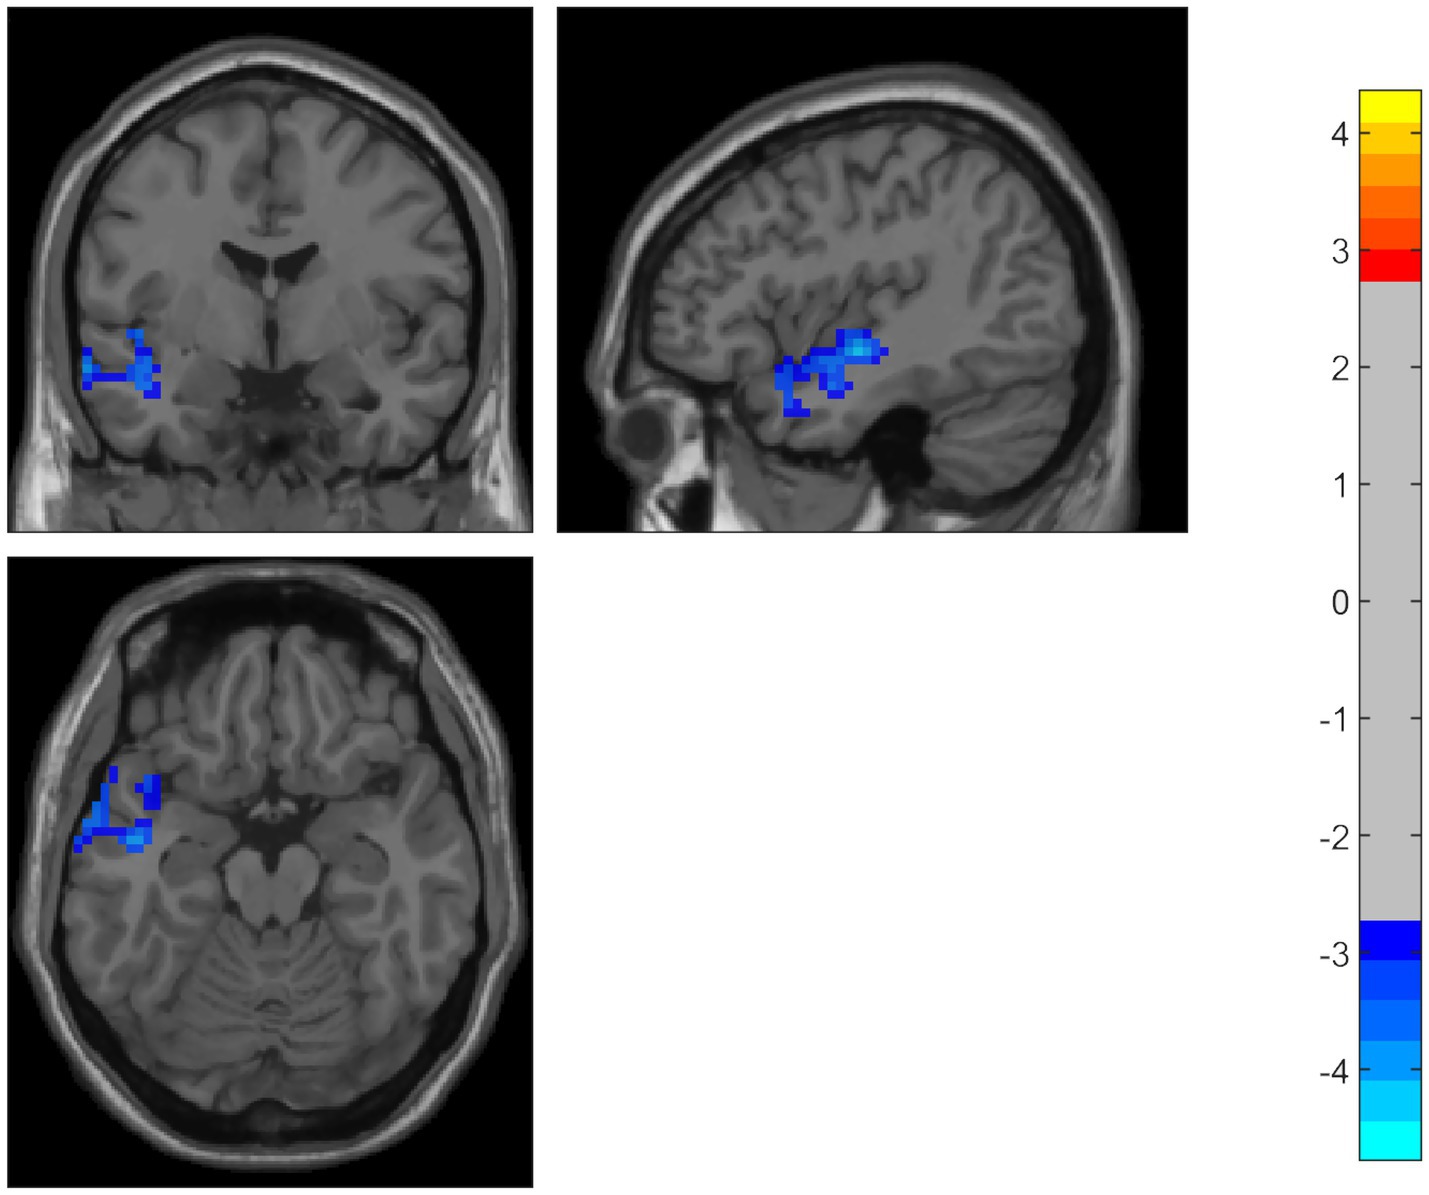

Compared to the HC group, the PD patients showed significantly decreased ALFF in the middle temporal gyrus, temporal pole, and superior temporal gyrus on the left side. Using the temporal pole as the ROI, PD patients also exhibited decreased connectivity between the temporal pole and the superior frontal gyrus (SFG), dorsolateral supplementary motor area (SMA), and precentral gyrus on the right side (GRF correction, p < 0.05) (Table 2 and Figures 1, 2).

Figure 1. Compared to the HC group, PD patients showed significantly decreased ALFF in the middle temporal gyrus, temporal pole, and superior temporal gyrus on the left side. The color bar represents T-values. Brighter colors represent higher values.